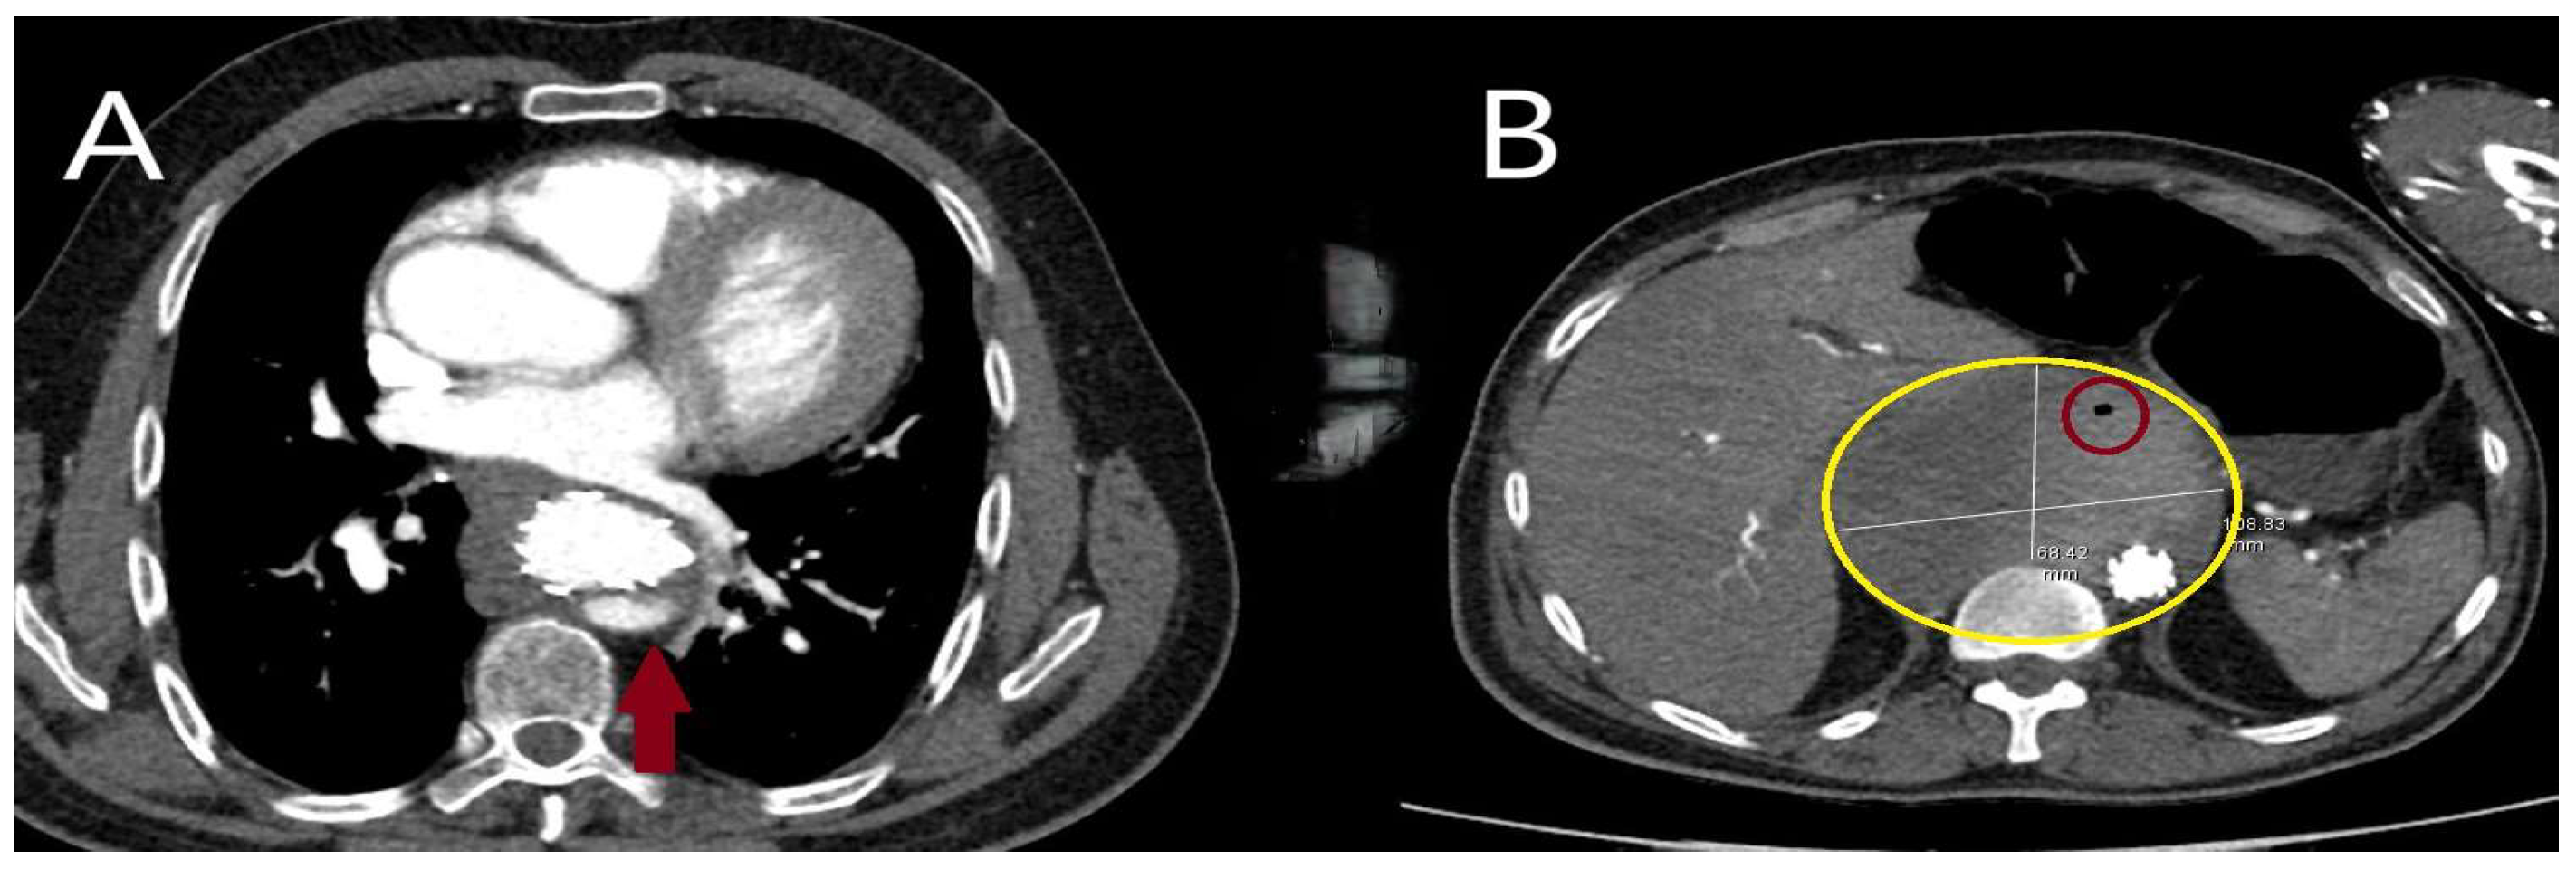

5.2.3. Computed Tomography

- Sathiadoss, P.; Haroon, M.; Wongwaisayawan, S.; Krishna, S.; Sheikh, A.M. Multidetector Computed Tomography in Traumatic and Nontraumatic Aortic Emergencies: Emphasis on Acute Aortic Syndromes. Can. Assoc. Radiol. J. 2020, 71, 322–334. [Google Scholar] [CrossRef] [PubMed]

- Ko, J.P.; Goldstein, J.M.; Latson, L.A., Jr.; Azour, L.; Gozansky, E.K.; Moore, W.; Patel, S.; Hutchinson, B. Chest CT angiography for acute aortic pathologic conditions: Pearls and pitfalls. Radiographics 2021, 41, 399–424. [Google Scholar] [CrossRef] [PubMed]

- Dreisbach, J.G.; Rodrigues, J.C.L.; Roditi, G. Emergency CT misdiagnosis in acute aortic syndrome. Br. J. Radiol. 2021, 94, 20201294. [Google Scholar] [CrossRef]